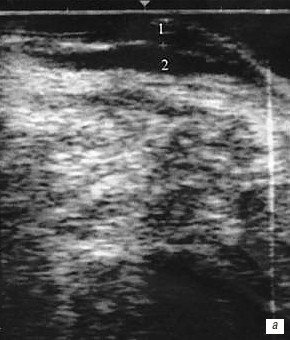

При ультразвуковом исследовании стенка анального канала имеет четырехслойную структуру. Первый слой, представленный сигналами средней эхогенности, соответствует эпителию и подэпителиальной соединительной ткани. Второй слой, не содержащий отраженных сигналов, представляет собой внутренний сфинктер. За ним определяется полоса средней эхогенности, которая соответствует продольной мышце. Далее идет полоса, представленная сигналами повышенной эхогенности, соответствующая наружному сфинктеру (рис. 1). Ниже располагаются мышцы, образующие тазовое дно [5]. Верхней и нижней границами анального канала считали проксимальный край внутреннего сфинктера и край анального отверстия, что соответствует "хирургическому" понятию запирательного канала.

Рис. 1. Ультрасонограмма продольного сечения анального канала, эндоректальное исследование.

1 - внутренний сфинктер;

2 - наружный сфинктер;

3 - продольная мышца.